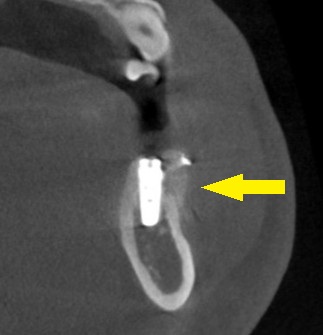

CTを撮影してみると、確かに、骨幅が狭く、十分な骨の厚みを確保してインプラントを長期に安定した状態にしたいとなると、骨を増やす手術が必要でした。

人工骨を使用しての骨造成術を併用して、インプラント埋入を行なうことで了承されましたので、本日、同手術を施行しました。

下の写真に手術前後のCTを示します。